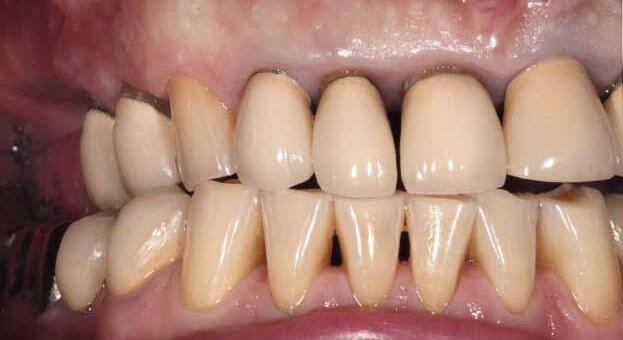

Fig 1. Patient anterior situation. Two anterior crowns fractured off.

Fig 3. Provisional restorations on central incisors and gingival images. The gingival contours were optimal, and the gingival phenotype was thick.